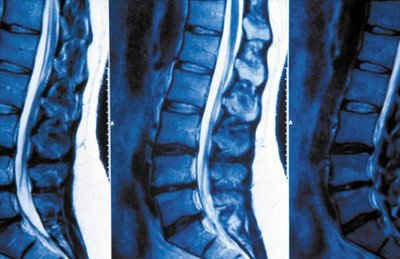

5、脊髓造影、腰椎闻盘CT平扫或腰核磁共振检查为阳性结果并与受累神经根的临床症状和体征相符合。